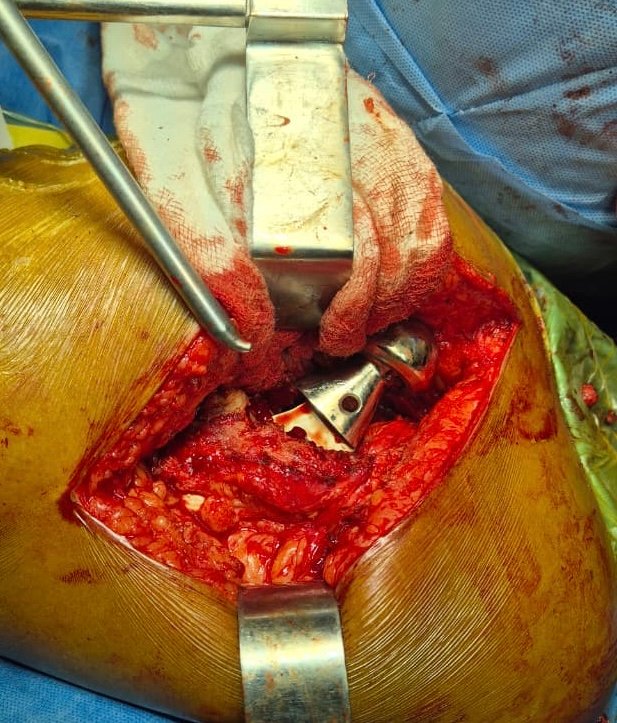

Intra-Op (Photos)

Removal of Fixed Bipolar Prosthesis

Extracted Steam